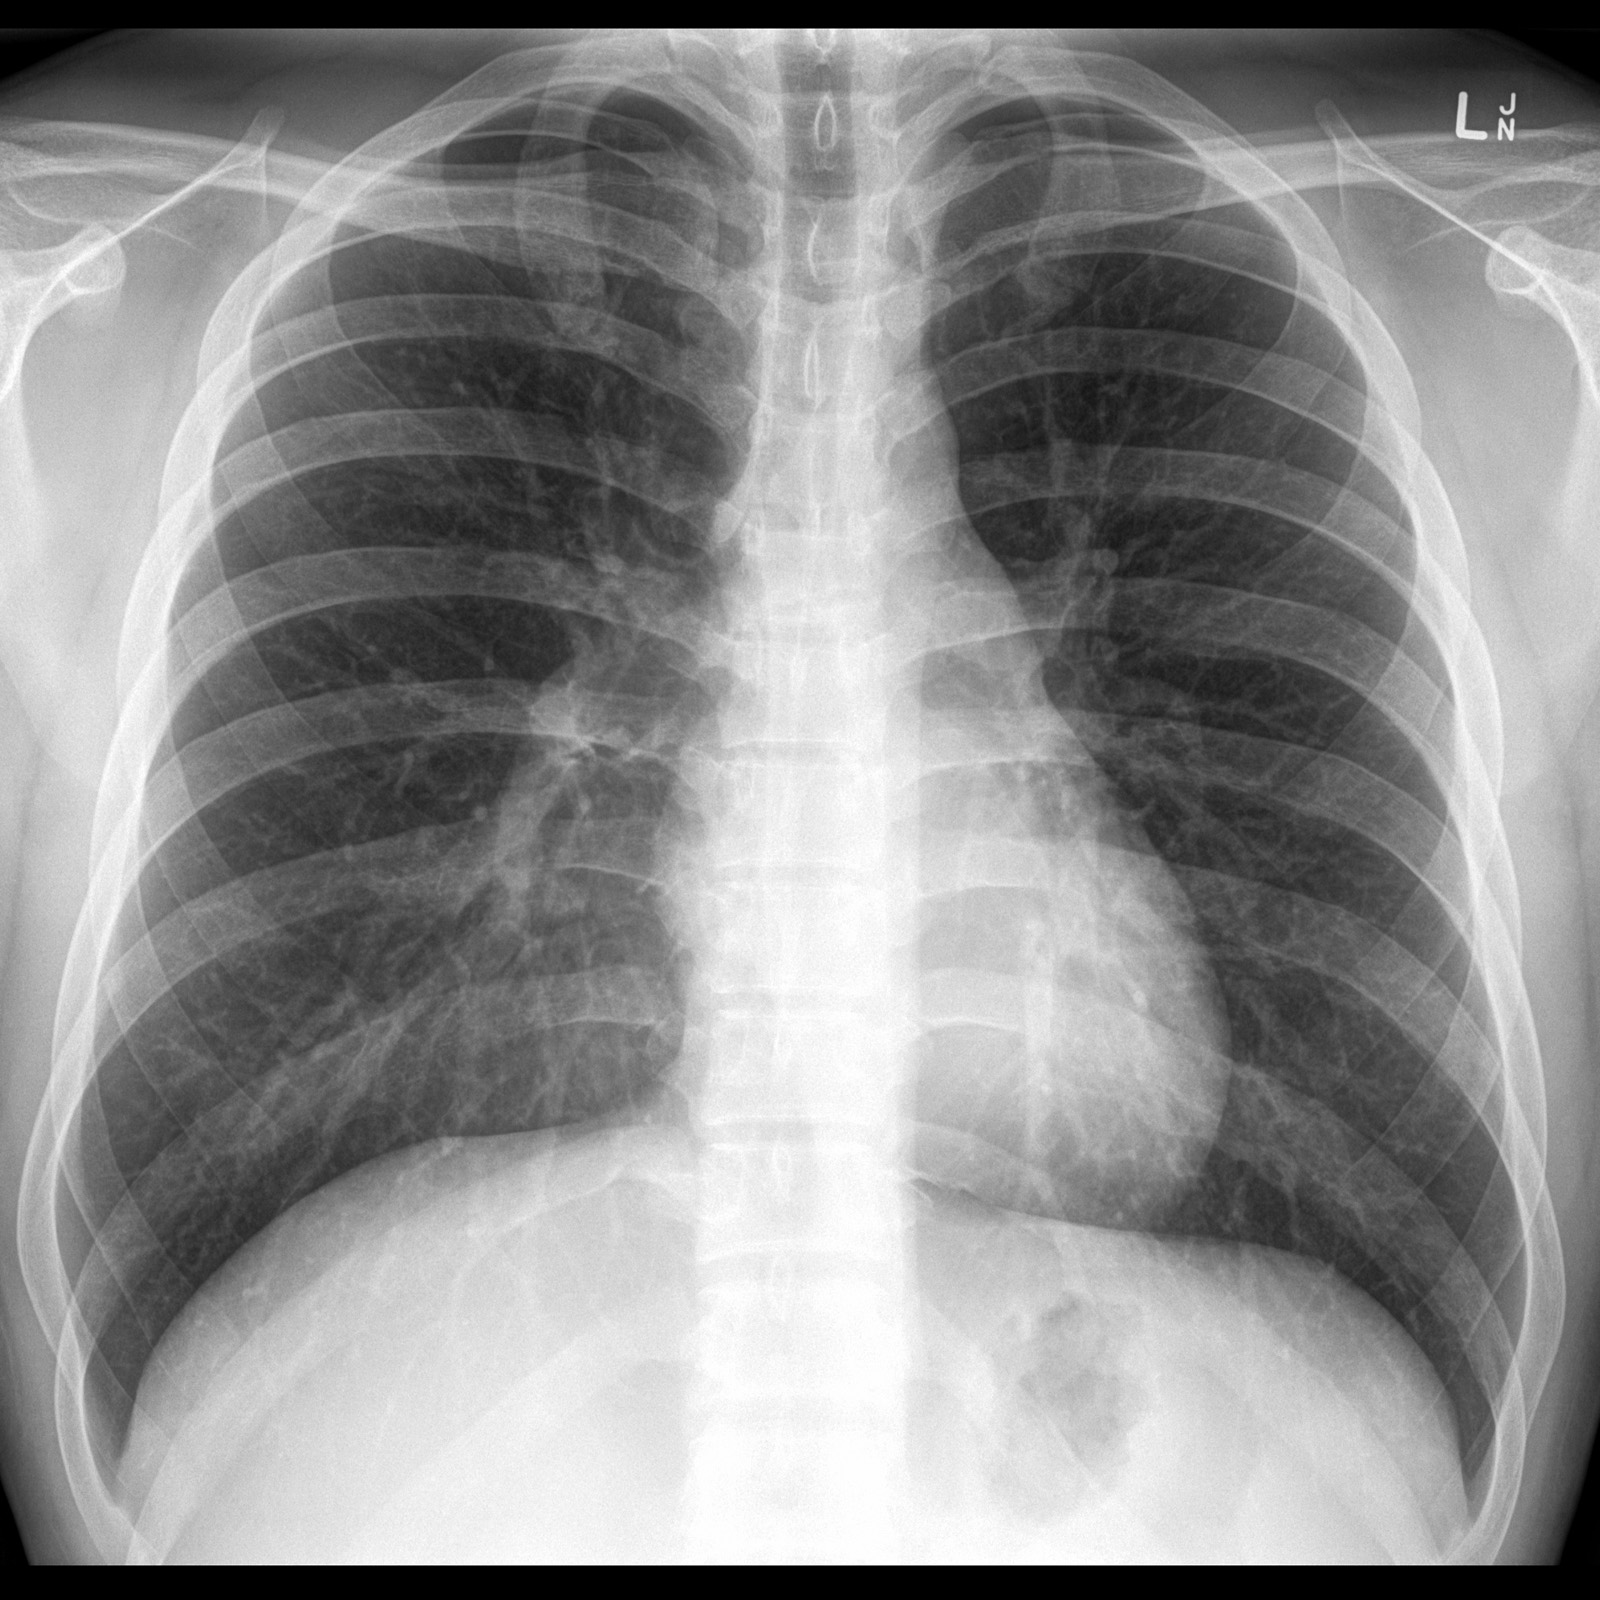

نضع بين ايديكم مجموعة الصور الاضافية على السلايدات التي تم شرحها في X-ray session :

Normal